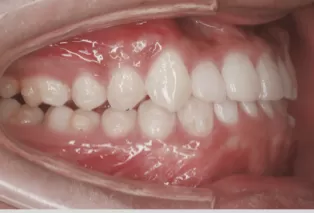

Photos intra-orales